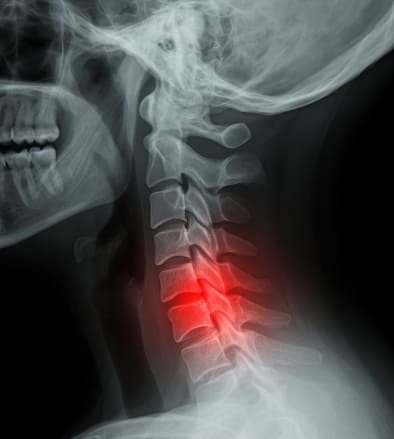

목디스크는 현대인에게 매우 흔하게 발생하는 질환으로, 장시간 스마트폰 사용이나 잘못된 자세로 인해 경추(목뼈)의 디스크가 탈출해 신경을 압박하면서 다양한 증상이 나타납니다. 목디스크 증상은 단순한 목 통증을 넘어 어깨 통증, 팔 저림, 두통, 심하면 손의 감각 이상까지 동반되며 삶의 질을 급격히 떨어뜨릴 수 있어 조기 발견과 적절한 치료가 매우 중요합니다. 오늘은 목디스크 증상과 목디스크 치료방법을 중심으로 정확한 정보와 효과적인 치료 접근법을 다루어 보겠습니다.

목디스크는 의학적으로 '경추추간판 탈출증'이라 불리며, 목뼈 사이에 위치한 디스크(추간판)가 돌출되어 신경을 압박하는 질환입니다. 대부분 퇴행성 변화나 자세 불균형에 의해 발생하며, 목디스크 증상은 생각보다 다양하고 광범위하게 나타날 수 있습니다. 목디스크 치료방법은 증상의 강도와 지속 여부에 따라 달라지므로, 정확한 진단이 중요합니다.

이러한 원인으로 인해 디스크가 돌출되면, 신경을 자극하며 다양한 목디스크 증상이 발생하게 됩니다.